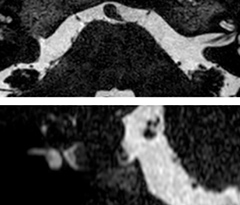

In this example, the optional 3D multishot susceptibility weighted sequence with 0.6 mm isotropic voxels is 2 lesions with a central vein sign (arrows) and one lesion with a phase-rim sign (arrowhead). The total scan time, including SmartBrain and axial PD/T2 3mm, is 11:10 min. and is 18:30 min. with the optional 3D PSIR and 3D SWI multishot included.

“We used to have long examination times for certain types of patients, a few lasting more than 40 minutes,” says Dr. Savatovsky. “What is remarkable, is that now all these examinations are below 30 minutes, which opens up opportunity to add more sequences when needed. It’s really hard to keep a patient for more than 40 minutes in the scanner, but because we have now cut scan times by at least 10 minutes, we can add more sequences without making the exam too long. And this is where the new system helps us make a difference. Examples include our examinations for informing brain tumor classification or giant cell arteritis workup, or for intracranial wall imaging – so in patients where we need several advanced sequences or high resolution sequences.” “We added three additional sequences in our brain neoplasm classification exam: a 3D SWI sequence, APT and ASL on top of 3D morphologic sequences, an isotropic DSC (dynamic susceptibility contrast) and multivoxel spectroscopy. I think that in patients that need a classification for brain mass, for example, we can provide a more detailed and confident diagnosis than before, allowing the clinicians to decide for either a medical workup if no tumor is suspected, or for neurosurgery as soon as possible if a neoplasm is suspected.” “In multiple sclerosis patients, we increasingly include a multishot susceptibility sequence [3] in our routine cases, thanks to the shorter scan times. Our abbreviated MS protocol for brain is around 8 to 9 minutes, so we can ask for one or two additional sequences to visualize the central veins, or to get an additional contrast to better depict posterior fossa lesions. In cases of white matter lesions of unknown significance on FLAIR images, for example when we see high signal hyperintensities in the brain, we can add on more advanced sequences such as PSIR (phase sensitive inversion recovery) or susceptibility-weighted sequences to help us in distinguishing between MS and nonspecific or vascular abnormalities in these inflammatory cases.”